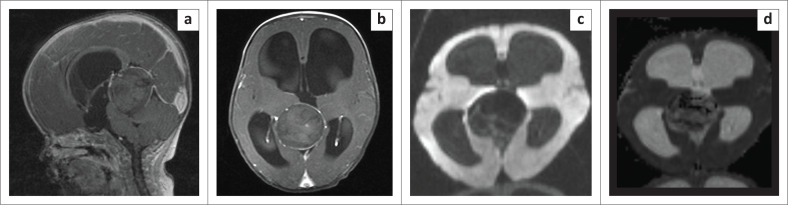

盖伦静脉动脉瘤畸形(VGAM)是一种罕见的先天性畸形,其特征是原始脉络膜动脉和正中前脑静脉(盖伦静脉的胚胎前体)之间的动静脉瘘。血管内技术改变了这些患者的治疗方法,改善了预后。一名八个月大的 VGAM 患者在使用乙烯-乙烯醇共聚物(EVOH)进行血管内栓塞治疗后,出现了罕见的并发症--化学脓肿。经保守治疗后,临床效果良好:贡献:EVOH栓塞术后的化学脓肿很少见,影像学鉴别包括脑脓肿和玛瑙肉芽肿。了解并成功识别这一实体至关重要,因为其治疗和预后各不相同。化学脓肿可采取保守治疗,预后良好。

Vein of Galen aneurysmal malformation (VGAM) is a rare congenital malformation characterised by arteriovenous fistulas between primitive choroidal arteries and the median prosencephalic vein, the embryonic precursor to the vein of Galen. Endovascular techniques have changed the management of these patients with improved prognosis. An eight-month-old with VGAM managed by endovascular embolisation using ethylene vinyl alcohol copolymer (EVOH) developed a chemical abscess - a rare complication. It was managed conservatively and showed promising clinical outcome.

Contribution: Chemical abscesses following EVOH embolisation are scarce - with imaging differentials, which include brain abscess and onyx granuloma. Knowledge and successful identification of this entity are essential as its management as prognoses differ. Chemical abscess is managed conservatively and has a good prognosis.